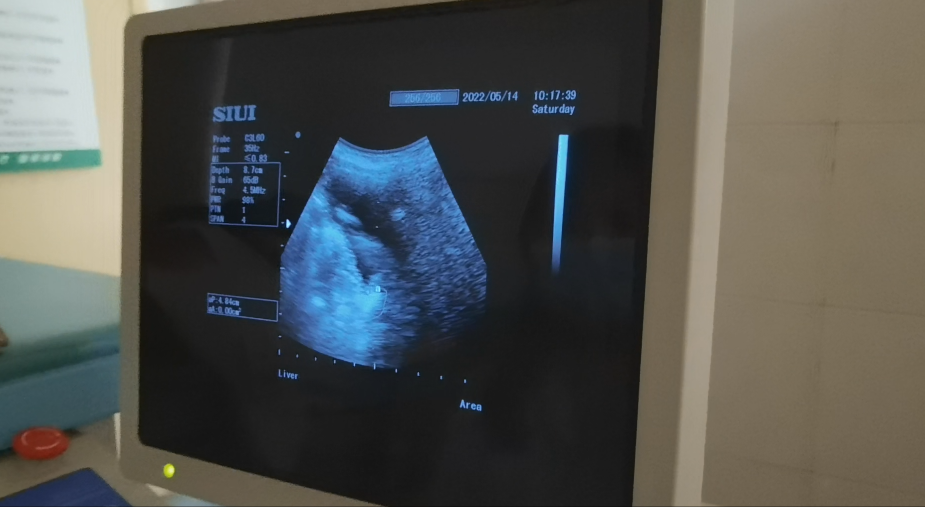

经彩超检查显示宝宝右侧输尿管下段结石,大小为1.2*0.8cm